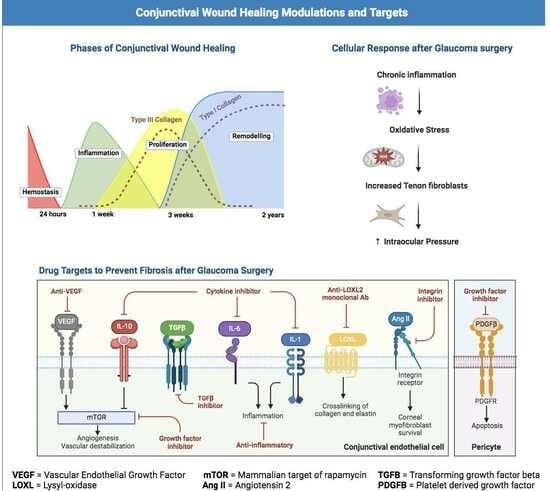

3.1. Overview of the Wound Healing Process

3.1.1. Hemostasis

3.1.2. Inflammation

3.1.3. Proliferation

3.1.4. Remodeling

3.2. Fibrosis

3.7. Experimental Wound Healing Agents

3.8. Future Directions